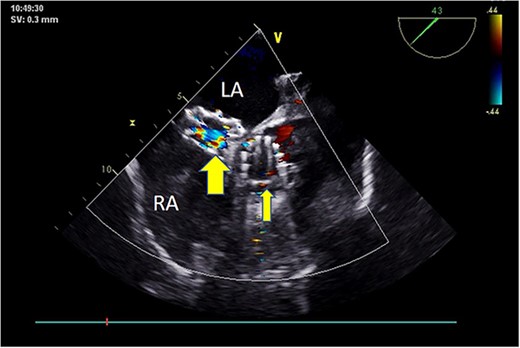

Postoperatively, imaging studies, including TEE and digital subtraction angiography (DSA), confirmed normalization of aortic valve flow velocity and pressure gradients, with the absence of aortic regurgitation (Fig. 7). Atrial shunting disappeared, and there was no involvement of the mitral or tricuspid valves. Both the self-expanding valve prosthesis and the closure device were stably positioned, and the surgical outcome was deemed successful (Fig. 8). One month after surgery, the patient’s symptoms of chest tightness and shortness of breath had resolved.

Postoperative TEE: Short-axis TEE displays circular echoes in the self-expanding valve (thick arrow) with good morphology and position. The sealing umbrella (thin arrow) maintains a proper shape and fixed position, eliminating left-to-right atrial-level shunt.